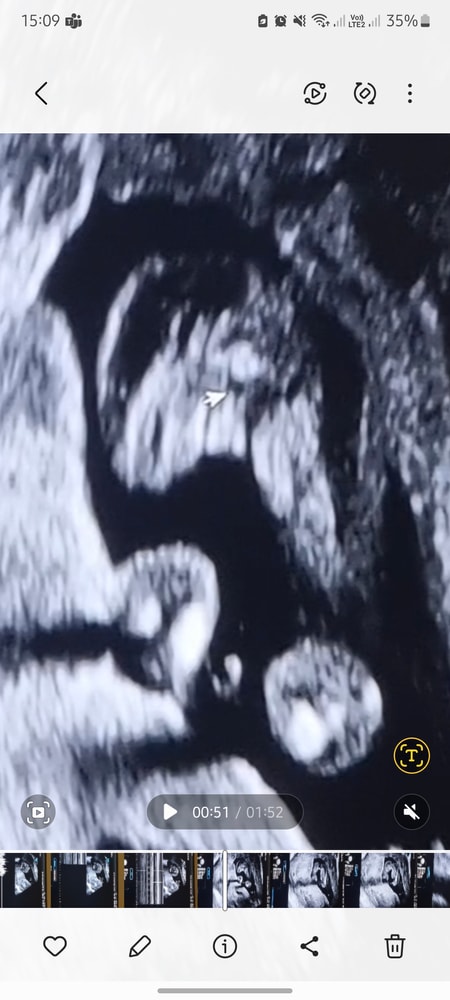

Пол по узи

Пол малышаДевочка ведь? А то я уже своим глазам не верю.

Курсор указывает на причинное место

Это ведь не пуповина какая, точно девочка?

Ничего не торчит)

Вряд-ли бы малыш подтянул бы пенис)

Потому, девочка)